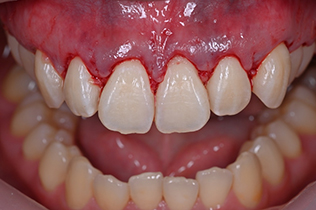

STEP 3

- 手術

- ガミースマイル改善のための外科手術をおこないます。

笑った時に歯茎が見えてしまうガミースマイルを改善したいとのことでご来院された患者様です。術後も大変満足していただきました。